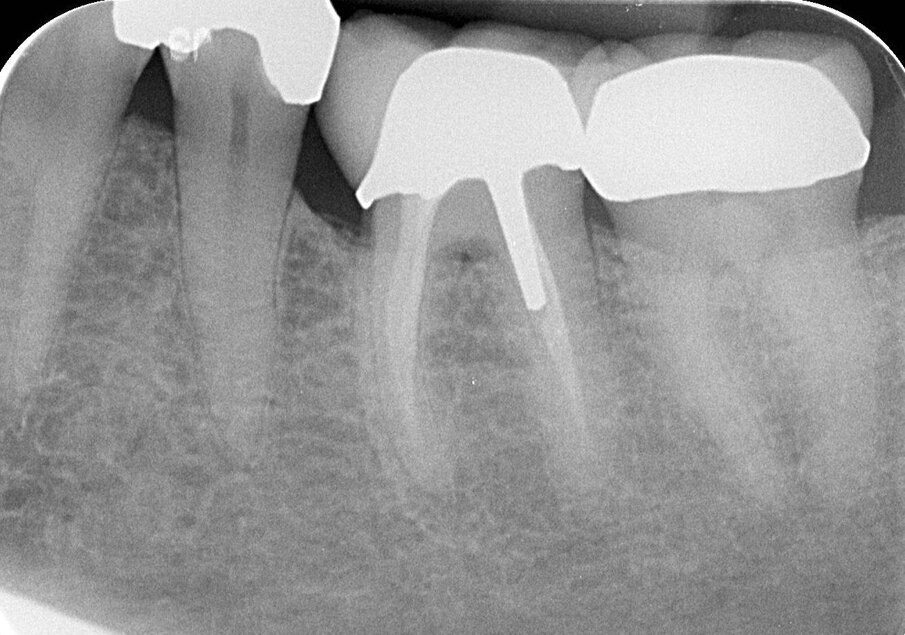

Het plan was om de perforatie, die deels subcrestaal lag, op te nemen in de outline van de kroon (afb. 4). In een daaropvolgende zitting deed ik aan de mesiale zijde van de 36 een kroonverlenging, met als doel om het perforatieoppervlak supracrestaal te brengen, en zo beter toegankelijk te maken voor een volledige omslijping met een schouderbevelpreparatie. De wondgenezing verliep ongestoord en de patiënt kreeg instructie over de interdentale reiniging van het behandelde gebied. Een maand later werd met behulp van een edelmetalen wortelstift (afb. 5) een Duralay opbouw gemaakt, die vervolgens werd aangegoten tot een edelmetalen stiftopbouw en geplaatst werd met zinkfosfaat cement. Weer drie weken later werd de volledige gouden kroon gecementeerd met zinkfosfaat cement (afb. 6). De patiënt kon de interdentale ruimte uitstekend schoonhouden met ragers.

Afb. 4: Bitewing waarop lokalisatie en omvang van de perforatie zichtbaar zijn